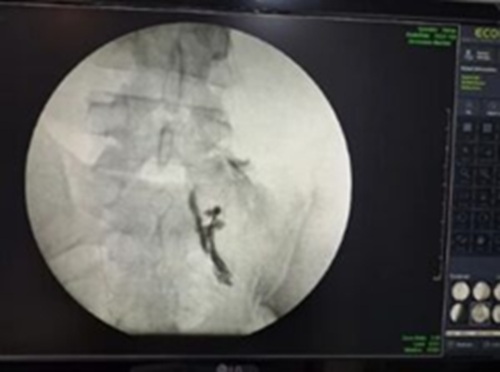

- بلوکهای عصبی تحت هدایت تصویر

- بلاک عصبی تحت فلوروسکوپی